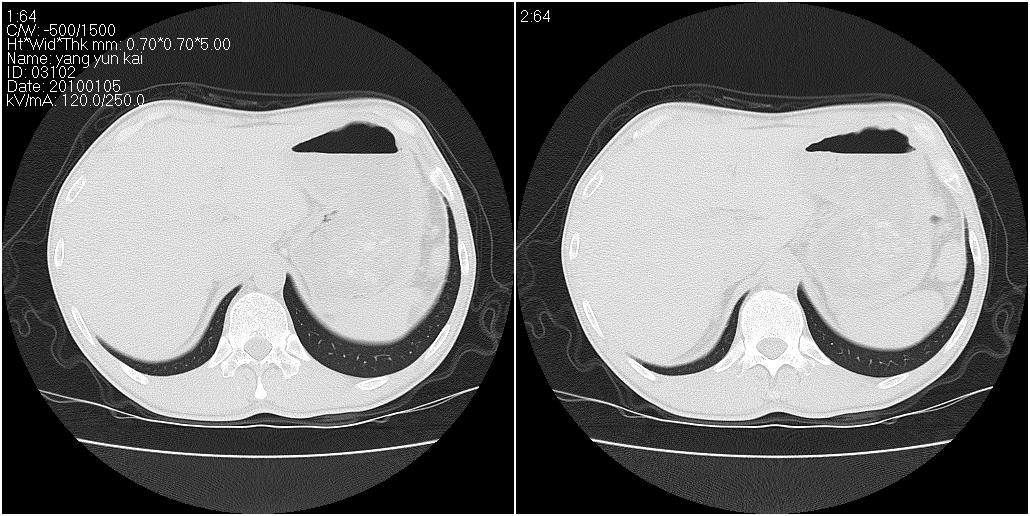

标题: CT23980:男性,47岁。近来咳痰、咳血,血沉增快(40左右),

男性,47岁。近来咳痰、咳血,血沉增快(40左右),痰中未检出结核杆菌。

两肺继发性肺结核并多发性结核球形成,部分病灶内空洞形成。

符合继发性结核表现部分空洞形成并播散